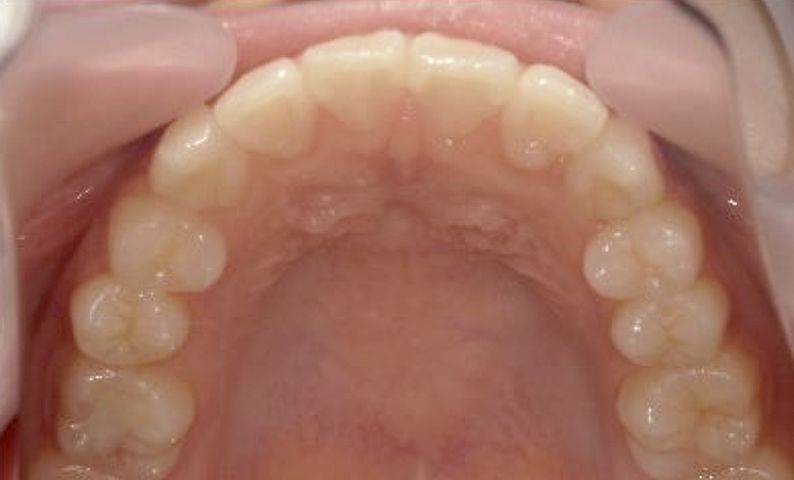

症例_025 上下顎の部分矯正

治療期間:13ヶ月金額:51万円+税女性前歯のガタガタ出っ歯

| Before | After |

|---|---|

|